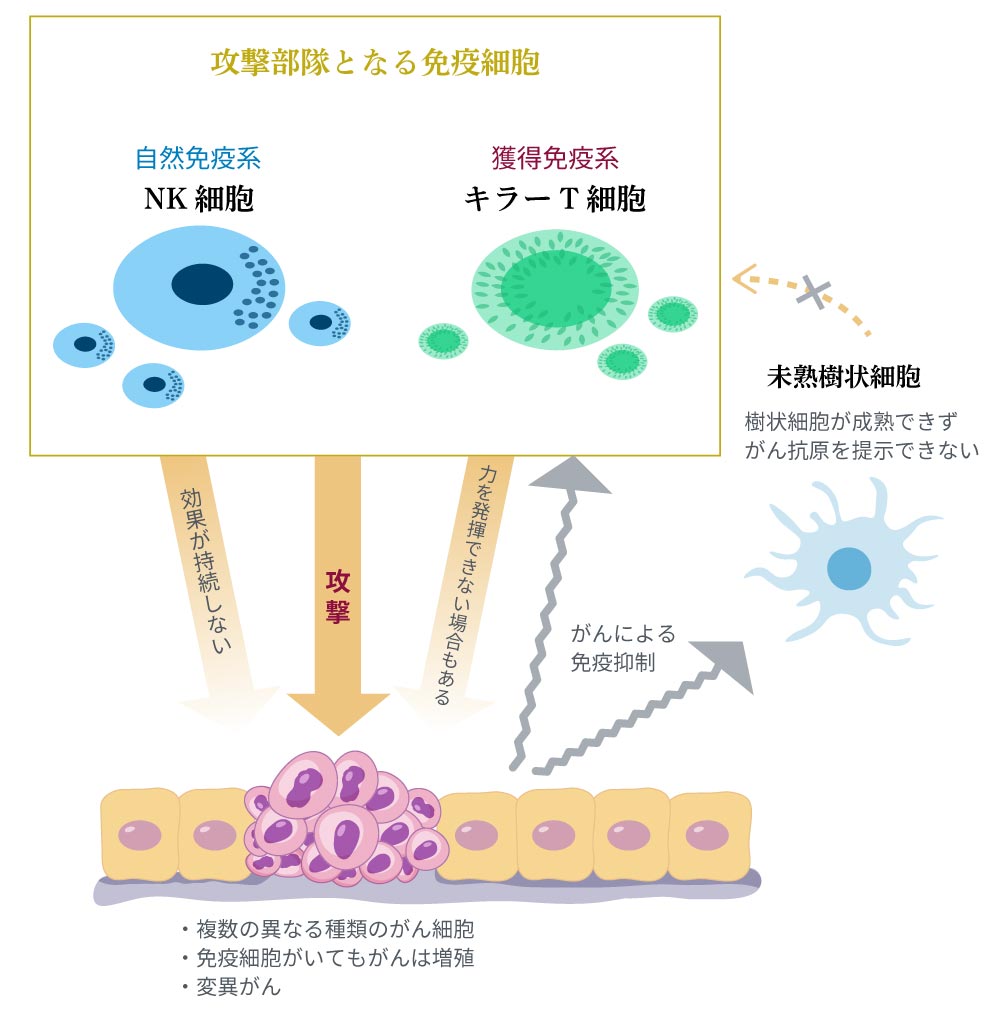

従来の免疫療法は、がんを標的として、がんを攻撃する免疫細胞を増やすという手法でした。攻撃部隊となるNK細胞やT細胞といった免疫細胞を体外で培養し、数を増やしてから体に戻す治療方法がとられます。しかし、この方法では以下のようなさまざまな理由で、十分な治療効果は得られませんでした。

- がん細胞の生残りや変異があり、がん細胞をすべて死滅させることができない

- 体に戻した免疫細胞には寿命があり、効果が持続しない。

- 免疫細胞ががん組織に到達できない場合も多い。

- がん組織が免疫不全状態になっていて、免疫細胞本来の力を発揮できない